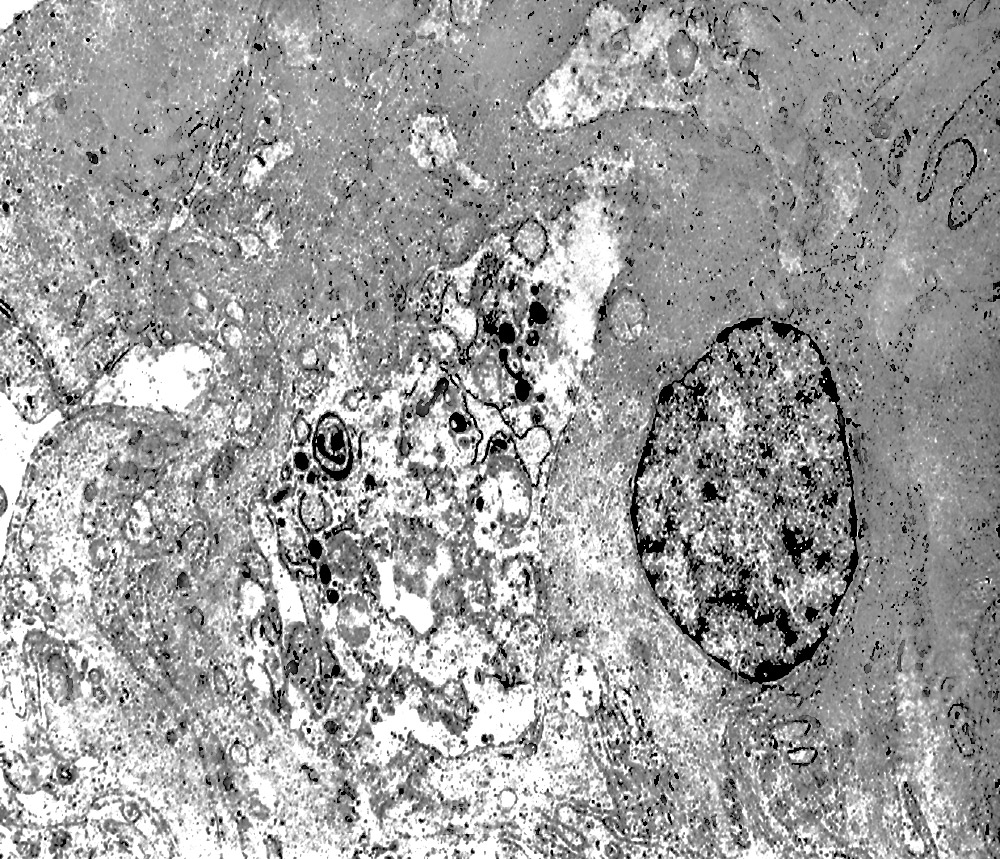

2/b AUTOLISOSOMA

Alcune cellule meningoteliali sono sedi, sopratutto a livello delle fasce periferiche, di ampie vescicole, di forma irregolare le quali sono demarcate da una membrana a mono-strato; gli spazi di queste vescicole sono in buona parte occupati da materiale amorfo, da frammenti filamentosi e da organuli intracitoplasmatici,tutto sottoposto a degradazione.

E’ possibile anche il reperto di elementi cellulari aventi il citoplasma occupato da ampie vescicole,delimitate da una membrana a monostrato, le quali sono ricolme di materiale amorfo,da strutture granulo-filamentose o da frammenti di organuli.

Non è raro il riscontro di cellule meningoteliali le quali hanno il citoplasma in buona parte occupato da una formazione cava,irregolarmente rotondeggiante; questa è delimitata da una spessa membrana ed è occupata da frammenti di citoplasma e da singoli organuli,tutto in corso di degradazione.

Nel contesto di alcune cellule coese,tutte contenenti focolai di micro e macroautofagia,è possibile rintracciare una di esse la quale è occupata da una ampia vescicola,a pareti frastagliate e lacerate, quasi ricolma di organuli e materiale filamentoso. Il citosol di tutte queste cellule è iperchiaro e gli organuli ivi contenuti sono in numero esiguo e mostrano segni morfologici di necrobiosi.